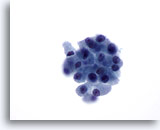

Positief voor maligniteit

Bij de monsters in deze categorie geldat dat bij resectie in bijna 100% van de gevallen een maligniteit wordt gevonden. Papillair carcinoom is de meest voorkomende maligniteit van de schildklier en heeft specifieke nucleaire kenmerken die eenvoudig zijn vast te stellen bij cytologische monsters. Andere maligniteiten waarvan de diagnose zeer nauwkeurig kan worden vastgesteld op basis van cytologie, zijn onder andere medullaire carcinomen, lymfomen, en metastatische carcinomen. Papillair carcinoom wordt gekenmerkt op ThinPrep door lagen en papillaire clusters van opeengepakte cellen met kernvergroting en molding, poederige chromatine, onregelmatige kerncelmembranen (met name kerngroeven en intranucleaire cytoplasmische inclusies), en kleine maar prominente en vaak eosinofiele nucleoli.[7] Daarentegen wordt medullair carcinoom gekenmerkt door geïsoleerde monomorfe plasmacytoïde cellen, die een hoge kern/cytoplasma-ratio hebben, excentrische kernen en grofkorrelige chromatine met of zonder een prominente nucleolus. Kleine, onopvallende granulen vullen het cytoplasma. Soms lijken de cellen spoelvormig, maar vertonen ze dezelfde nucleaire kenmerken. Lymfomen en metastatische carcinomen van de schildklier komen veel minder vaak voor. Hun cytologische kenmerken hangen af van het type en de plaats van oorsprong.